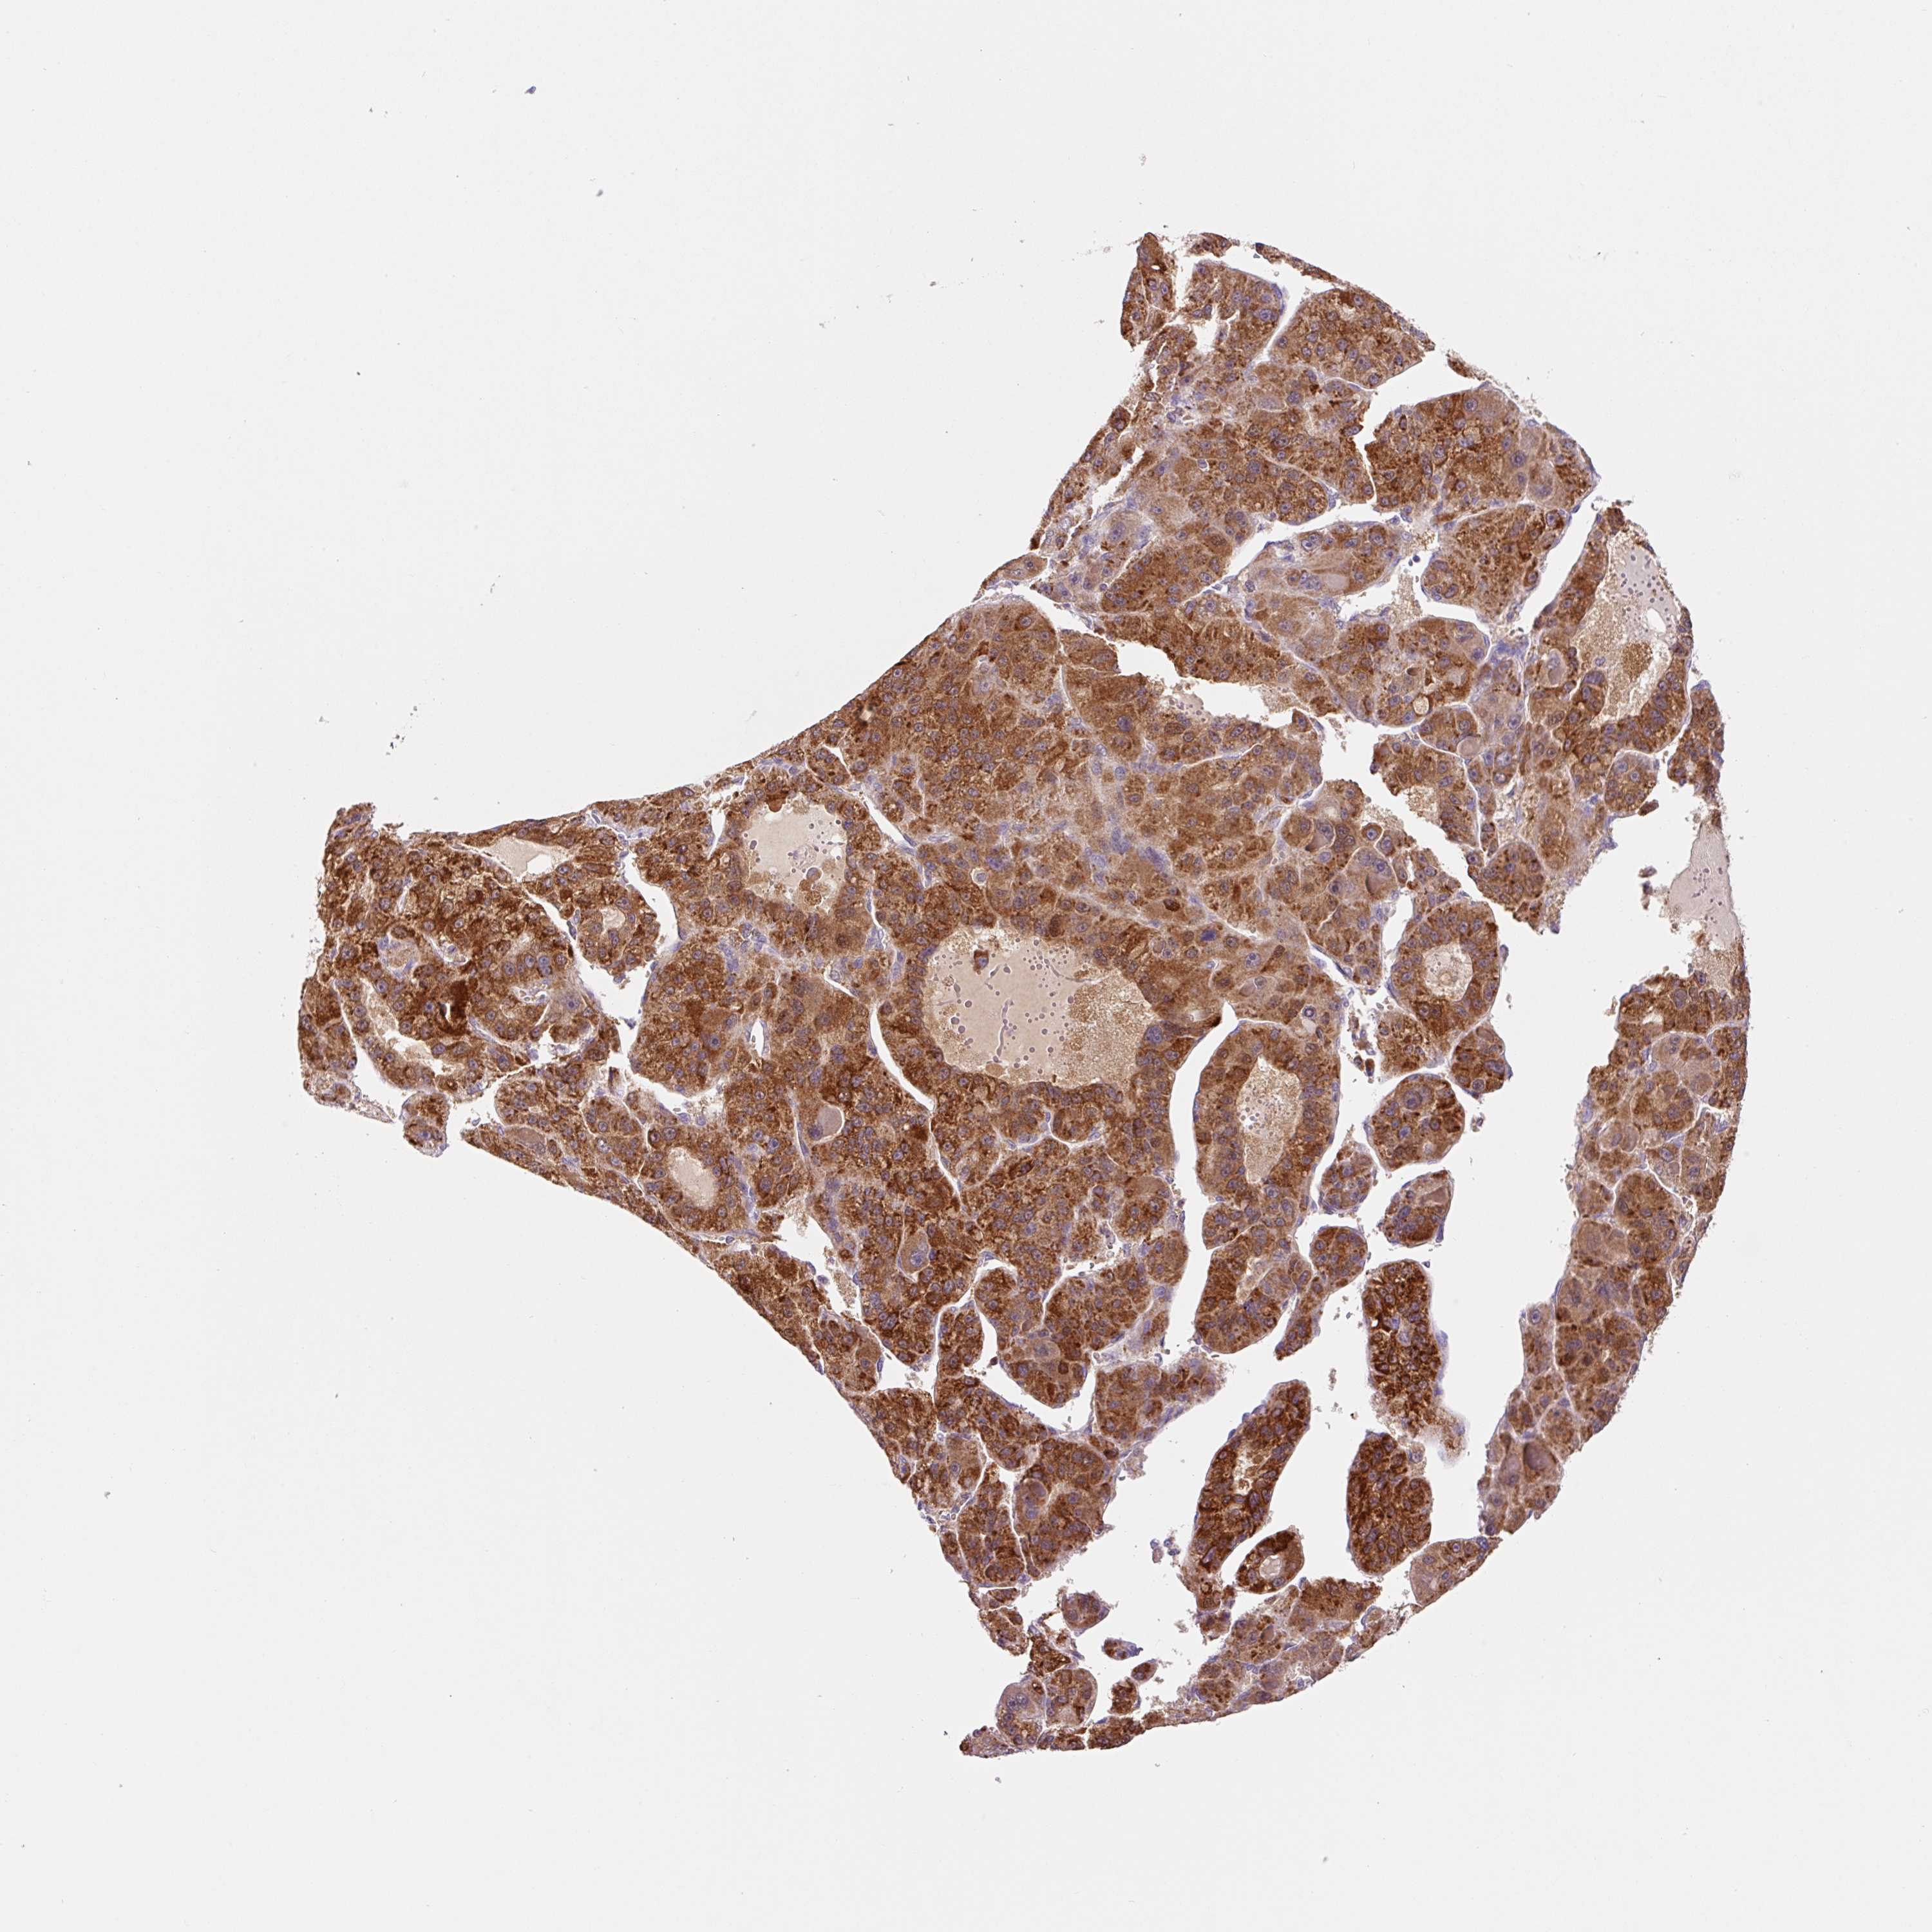

LIVER CANCER - Protein expressioni

A mouse-over function shows sample information and annotation data. Click on an image to view it in a full screen mode. Samples can be filtered based on level of antibody staining by selecting one or several of the following categories: high, medium, low and not detected. The assay and annotation is described here.

Note that samples used for immunohistochemistry by the Human Protein Atlas do not correspond to samples in the TCGA dataset.

Antibody stainingi

Antibody staining in the annotated cell types in the current human tissue is reported as not detected, low, medium, or high, based on conventional immunohistochemistry profiling in selected tissues. This score is based on the combination of the staining intensity and fraction of stained cells.

Each image is clickable and will lead to virtual microscopy that enables deeper exploration of all samples and also displays staining intensity scores, fraction scores and subcellular localization as well as patient and tissue information for each sample.

Antibody HPA051162

Antibody HPA053502

Antibody CAB018734

Staining

High

Medium

Low

Not detected

Intensity

Strong

Moderate

Weak

Negative

Quantity

>75%

75%-25%

<25%

None

Location

Nuclear

Cytoplasmic/membranous

Cytoplasmic/membranous,nuclear

Cholangiocarcinoma

Carcinoma, Hepatocellular, NOS